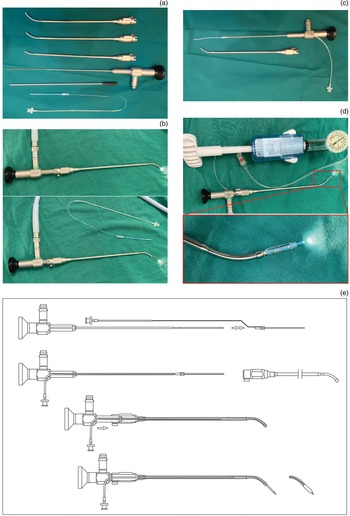

The Eustachian tube video endoscope consists of a hard segment and a soft segment (Figure 2a). The catheter has three angles, 30°, 45° and 60°, which can be adjusted to change the angle of the endoscopic soft segment to adapt to different Eustachian tubes (Figure 2b). The supporting balloon can be sleeved on the Eustachian tube video endoscope soft segment (Figure 2c), and used with the catheter to advance the matching balloon along the Eustachian tube video endoscope soft segment to the appropriate position of the Eustachian tube (Figure 2d). The schematic diagram and operational illustration of this equipment are shown in Figure 2e.

Figure 2. Structure of the Eustachian tube video endoscope and its supporting balloon. (a) The shape characteristics of the Eustachian tube video endoscope. (b) The catheter changing the angle of the Eustachian tube video endoscope soft segment. (c) Combination mode of Eustachian tube video endoscope and its supporting balloon. (d) The angle of the supporting balloon can change with the Eustachian tube video endoscope according to the catheter used. (e) Diagram of the equipment.